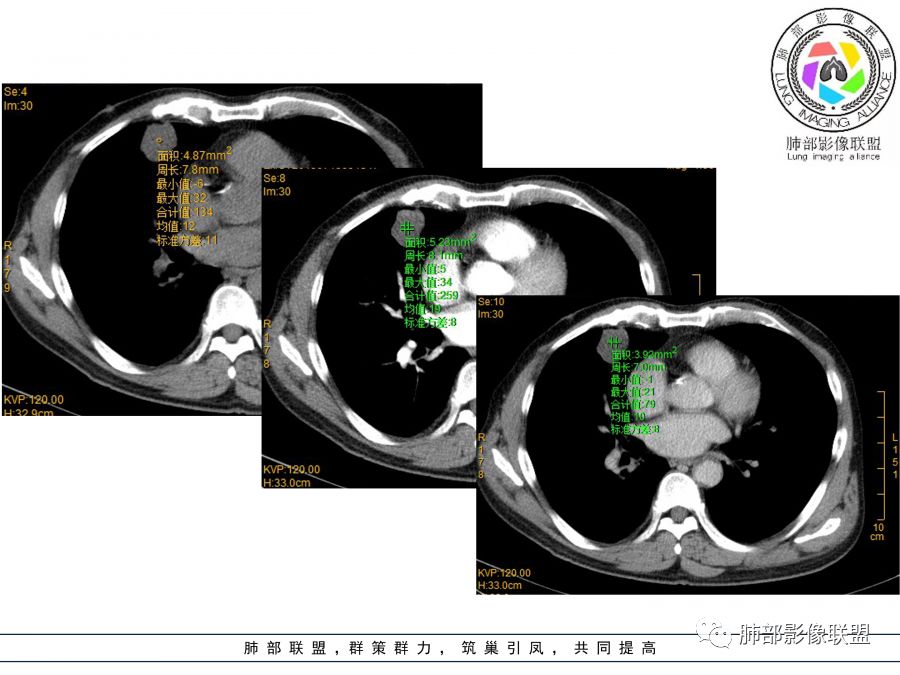

NSE确实比较高了,病灶边缘清晰,内部可见血管,点测ct值无强化,但肉眼可见肿瘤外周还是存在强化,考虑神经内分泌癌

目测这里还是有强化,其余地方强化幅度不是很明显

3.外侧可见血管进入,病灶局部轻度强化。